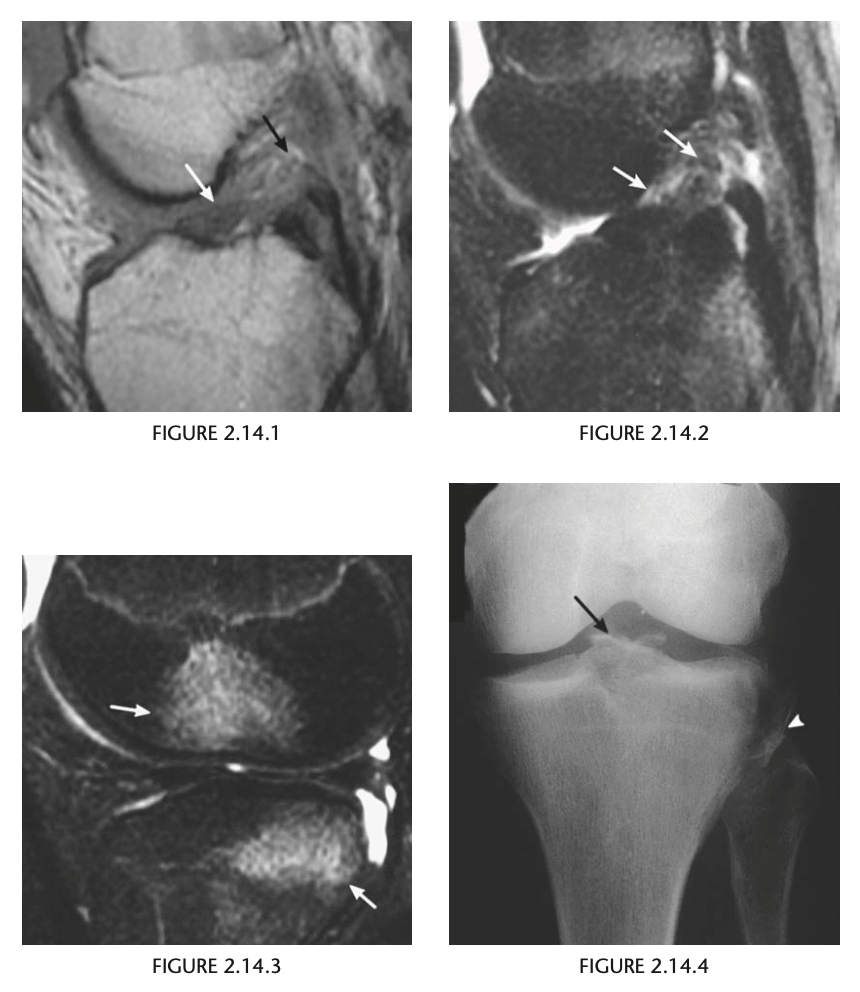

Full thickness tear of the ACL

Conventional radiographic findings of an ACL

tear include avulsion fractures from the femoral or

tibial attachment of the ACL (Fig. 2.14.4, arrow), the

Segond fracture (Fig. 2.14.4, arrowhead), or a deep

lateral sulcus sign (Fig. 2.14.5, arrow).